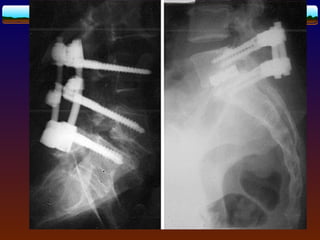

Surgical treatment ------Surgical goals pain reduction,  improvement of neurologic symptoms,  improvement in the quality of life. If attainment of these goals is unlikely, conservative treatment should be continued.

Indications  indications : --progressiveneurologic deficit --cauda equina syndrome. --slip >50% and progressive - persistent radiculopathy -persistent and unremitting lower-back -pain for more than 6 months, -disabling symptom-affect work,sport

Decompression Alone Laminectomy andPosterior Spinal Fusion (without Interpedicled Instrumentation( Decompression with Anterior and Posterior Spinal Fusion